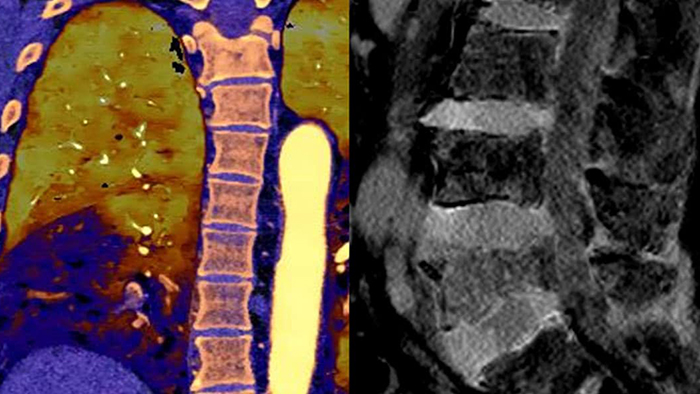

Spectral CT 7500 provides advanced diagnostic capabilities through a single spectral scan, enabling accurate diagnoses and expediting treatment times. Expand patient care with a one-stop solution across radiology, cardiology, oncology, neurology and trauma. Easy workflow with high image quality, low dose and spectral results. Scan in seconds as you normally would for conventional CT with immediate access to spectral CT results that can help eliminate the need for multiple CT scans or even additional scans from other modalities.

With Spectral CT 7500, a single spectral scan offers advanced diagnostic capabilities to help speed time to treatment. Expand patient care with a one-stop solution across radiology, cardiology, oncology, neurology and ED/trauma.

Simplify the patient care journey with Spectral CT 7500. Have layers of rich spectral results – on demand, with no special protocols. Spectral CT delivers true conventional and spectral insights for every patient and every scan with easy workflow.